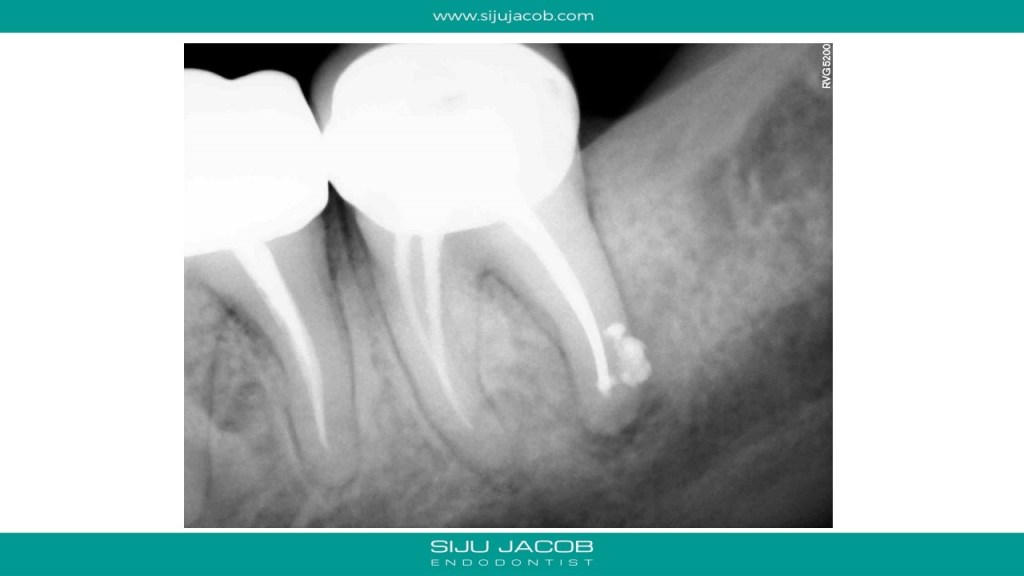

In the past, when we attempted Re-treatment, we used to re-treat all the canals. For the past 4-5 years, I’ve been doing mostly selective Re-treatment ie: treat only those roots or canals which need something to be done. Michael Trudeau calls it “Titrated Treatment”. Some of my friends call it “Image guided Treatment (IGT)”.

This patient had pain followed by a sinus tract on a previously endo treated and crowned mandibular second molar. The Distal root had a lesion. The Mesial root, although short, didn’t have any lesion. So, I decided to leave the mesials alone. I placed Calcium hydroxide, waited for the sinus to heal and then Obturated.